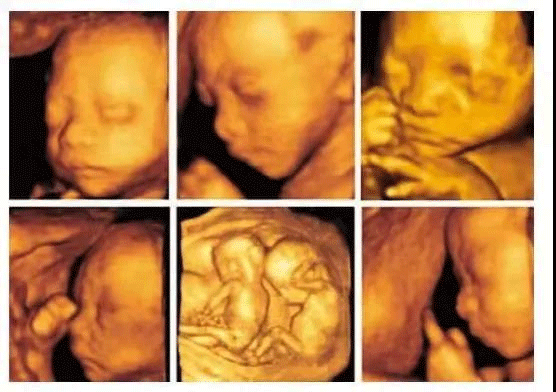

回答:孕期四维彩超是超声检查的一种,其成像技术能够让孕妇更加清晰的观察宝宝的生长发育情况。

除了对胎儿进行常规检查外,四维彩超和B超的区别在于其图像更加立体,能够对胎儿头面部立体成像,帮助医生动态观察宝宝神经系统情况,是孕早期胎儿排畸的重要检查手段,高档次的四维检查,还添加了时间维度参数,可以实时掌握胎儿活动图像。

在临床上,四维彩超的全称为四维彩色超声诊断仪,是目前世界上先进的超声检查设备,为胎儿是否有先天性心脏病、脊柱裂畸形等提供准确的科学依据,孕妇可以及早发现及时做处理,达到优生优育的目的。

3、面部是否存在畸形,我们都知道四维彩超的作用就是能够将胎儿的全身情况以非常清晰的形式展现出来,所以医生通过观察胎儿面部,测量双眼与眼眶是否等大、眼距信息、硬腭、软腭等,诊断脸部发育是否畸形;

四维彩超被称为“0岁胎儿的写真”,主要是用来观察宫内胎儿的生长情况,排出宝宝畸形,但很多准爸妈不知道四维彩超报告单怎么看,想要正确的读懂ri、bpd数据,首先你的打开方式要对。